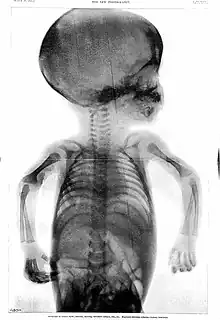

Rowland's career began in medical journalism while he was still a medical student when, in 1896, as Hart's intern, the year following the discovery of X-rays,[6] the BMJ appointed Rowland as "Special Commissioner" to produce a report on the clinical use of X-rays titled "Report on the Application of the New Photography in Medicine and Surgery".[3][6][lower-alpha 1] It was published in 17 parts between 8 February 1896 and 12 June 1897.[3] In May 1896, he founded the world's first X-ray journal, the Archives of Clinical Skiagraph, a radiology journal that preceded the British Journal of Radiology.[3][6] In the preface to the first issue, written in April 1896, he wrote that "the object of this publication is to put on record in permanent form some sort of the most striking applications of the new photography to the needs of medicine and surgery".[6] He coined the term "skiagraphy" to describe the making of X-ray pictures and wrote some of the early works on radiology.[3] Without any radiology experts or X-ray departments at the time, his journal became essential reading.[6]